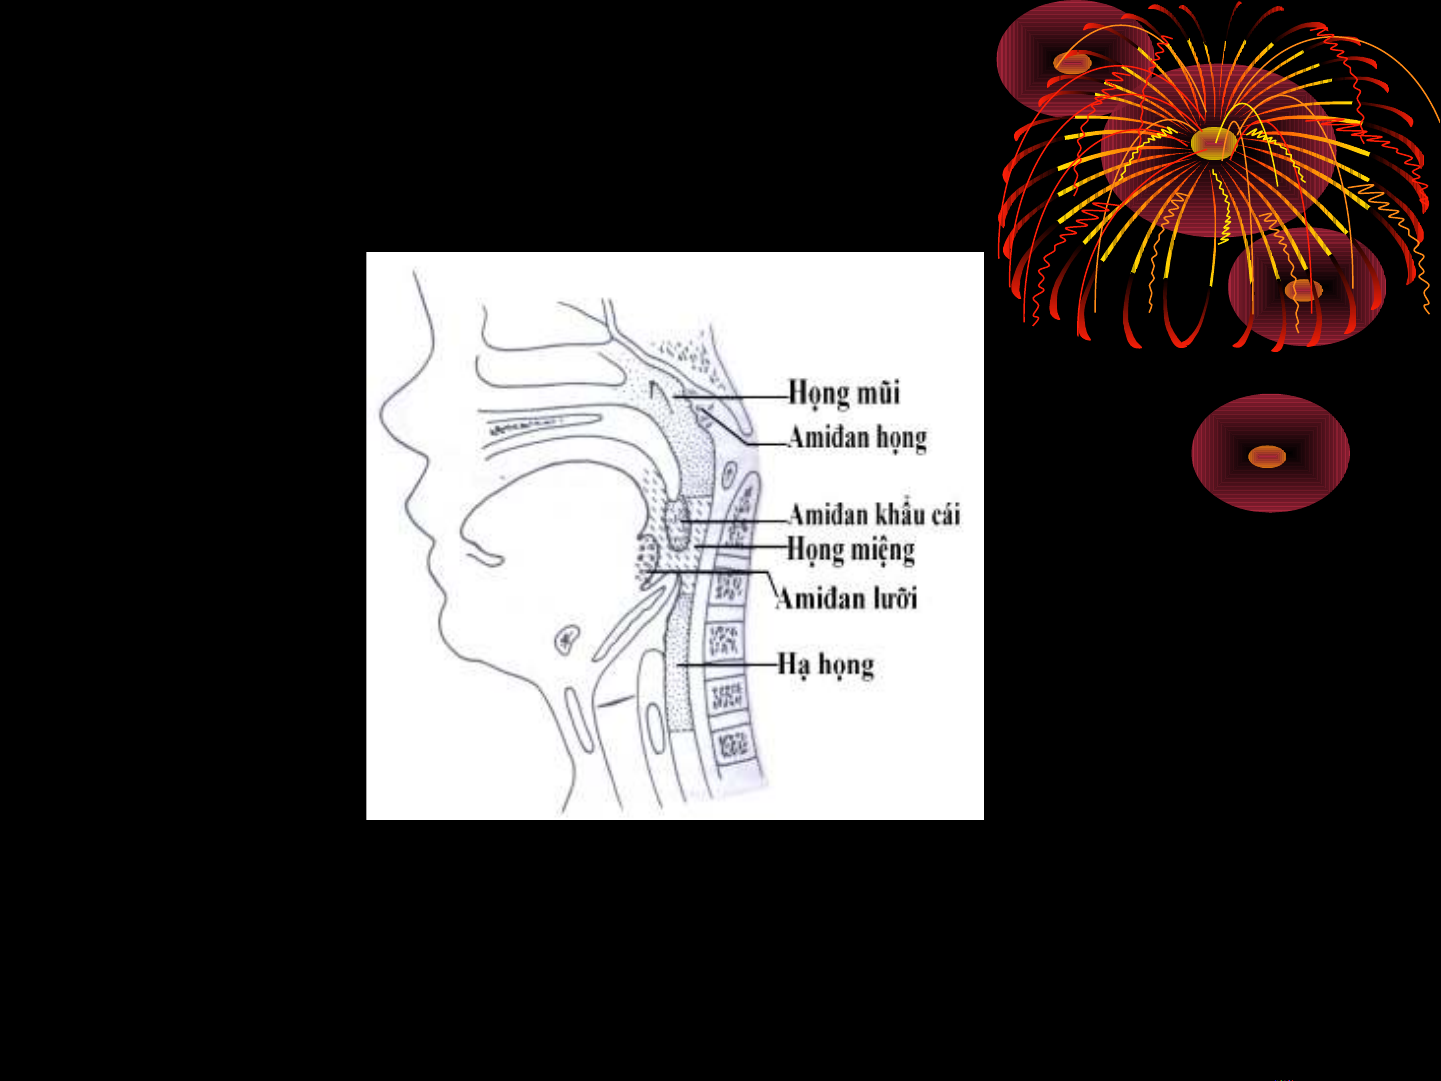

C QUAN LYMPHO HONGƠ

Amiđan-V.A vo ng Waldeyer

Ca c khôi mô lymphô amiđan chi nh cua vo ng Waldeyer : 6

C QUAN LYMPHO HONGƠ

Amiđan-V.A vo ng Waldeyer

Amiđan hong/Hanh nhân hâu (Tonsilla pharyngealis), VA: (1),

năm vo m hongơ .

Amiđan vo i/Hanh nhân vo i (Tonsilla tubaria), môt căp (2), năm

quanh lô vo i Eustachia trong hô Rosenmüller.

Amiđan khâu ca i/Hanh nhân khâu ca i (Tonsilla palatina), môt

căp (2), năm 2 phi a bên hong miêng ơ , th ng g i là ườ ọ Amiđan.

Amiđan l i/Hanh nhân l i ươ ươ (Tonsilla lingualis) (1), năm ơ

đa y l i.ươ

Ngoa i ra co n co môt sô đa m mô lympho rai ra c.